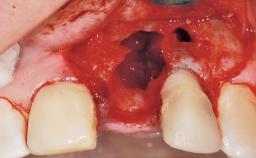

Immediate Flapless Placement of an Implant in a Maxillary Left Central Incisor Site

A 42-year-old female patient was referred to our clinic at the School of Dentistry of the University of São Paulo in November 2004, presenting a deficient restoration in the upper left central incisor. The clinical examination revealed no gingival retraction or any signs of gingival inflammation and, therefore, previous periodontal treatment was not considered. The patient presented a high lip line at full smile and a thin tissue biotype. This combination characterized a high-risk situation from an anatomic point of view, which required careful preoperative planning and cautious surgical execution.

Soft Tissue Grafting None

Soft Tissue Anatomy Intact Defective